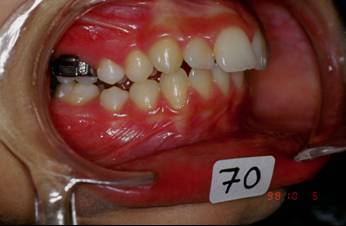

Je crois cette fois ca va marcher. Il s'agit d'une jeune fille de 12 ans, origine franco-libanaise, deja reglee depuis qqs mois. Classe II1 dentaire. Une demande majeure pour la patiente et sa maman: Les dents du haut sont trop en avant, il ne faut surtout pas les avancer ou les garder comme ca!!!

1 aswyzj - Eugenol

2 yzorem - Eugenol

3 uk1wzr - Eugenol

4 nsnllc - Eugenol